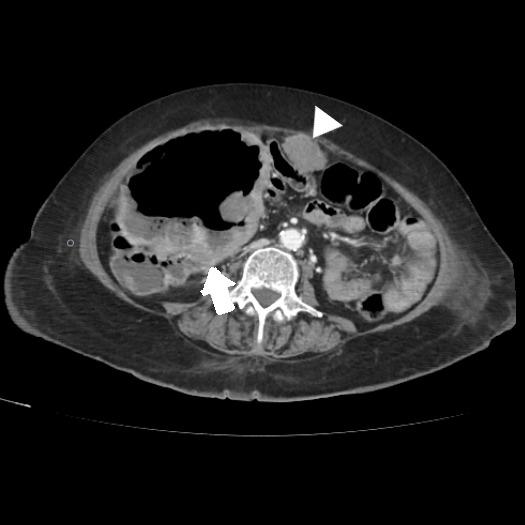

Cholecystocolonic fistula (CCF) is the second most common cholecystoenteric fistula, associated in most cases with stone disease. Symptoms are usually minimal or nonspecific, and preoperative diagnosis is uncommon. Although the incidence of FCC caused by gallbladder cancer comprises 1.7% of cases, it is necessary to suspect it in order to adopt the best therapeutic strategy.

胆囊结肠瘘(CCF)是第二常见的胆囊肠瘘,多数情况下与结石病相关。症状通常轻微或不具特异性,术前诊断并不常见。尽管胆囊癌导致的胆囊结肠瘘发病率占病例的1.7%,但为了采取最佳治疗策略,仍有必要怀疑此病。